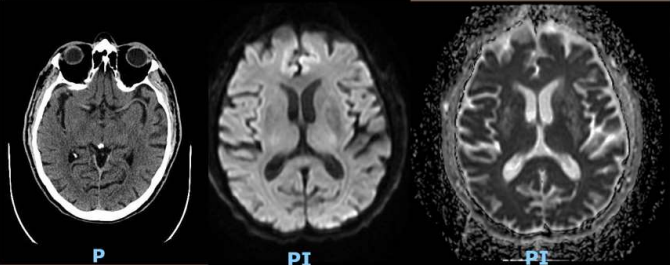

Our patient is an 80 year old gentleman with a prior history of coronary artery disease with previous coronarography 5 years ago on Clopidogrel 75 mg orally once daily, hypertension on Valsartan 80 mg orally once daily, dyslipidemia on Atorvastatin 40 mg orally once daily, allergy to penicillin, and severe symptomatic aortic stenosis stage D1 (high flow-high gradient),  presented for coronary angiography in preperation for Transcatherter Aortic Valve Implantation (TAVI). Patient arrived to the catheterization lab hemodynamically stable with a normal creatinine clearance and creatinine level of 0.83 mg/dL. Midazolam 1mg, fentanyl 25 mcg, and heparin 3,500 units were administered intravenously (IV). Radial access technique was adopted. The procedure lasted 25 minutes, and it was smooth and uneventful. Overall, 50 mL of contrast agent, Iodixanol (VISIPAQUE 320 mg/mL) was administered intra-arterially. Findings of the coronary angiography were consistent with diffuse aneurysmal atherosclerosis with some sluggish flow but no significant lesion. In the medical ward, 2 hours after the procedure, the patient started to develop disorientation and attention deficit, progressing rapidly into nausea, bitemporal headache and complete vision loss. Vital signs were in normal ranges and neurological examination revealed intact cerebellar, sensory, motor and reflex powers with normal bilateral pupil reactivity to light. Fundoscopic examination showed normal cup/disk ratio of the optic nerve head with good color and normal clear neuroretinal rim, flat macula with bright reflex and normal color, normal retinal vessels with no hemorrhage and no signs of arterial or venous occlusion, and no retinal detachments or tears. Patient was transferred for an urgent CT and MRI (figure 1) of the brain, which showed minimal small vessel disease and age-related parenchymal atrophy, no acute ischemic or hemorrhagic process identified, and no evidence of retained contrast material.

Figure 1: A- Axial cut of CT scan without contrast. B- Axial Diffusion-weighted imaging. C- Apparent diffusion coefficient map